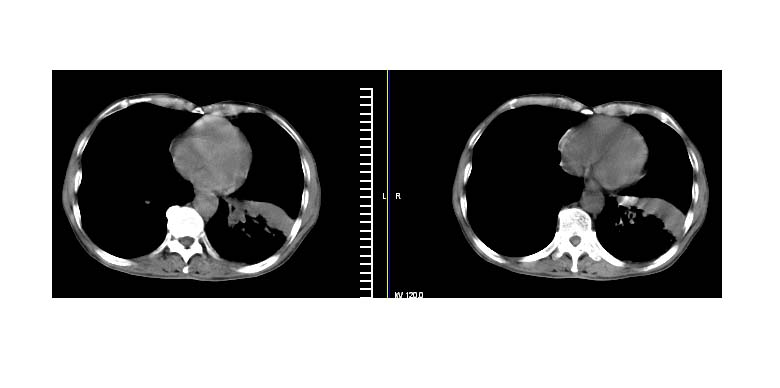

标题: CT11019:男性,66岁。发烧5-6天。治疗后无明显好转。 [打印本页]

标题: CT11019:男性,66岁。发烧5-6天。治疗后无明显好转。

左下肺中央型肺癌伴阻塞性肺炎\\肺不张可能性大,建议支纤镜检查.

1.左肺门似可见一小块影,由此考虑中央型肺ca并阻塞性肺炎改变;

2.左下叶背段肺tb(干酪性肺炎)?

3.单纯肺感染?建议进一步检查。

左下肺中心性肺癌伴下肺不张及周围阻塞性炎症

左下肺中央型肺癌伴阻塞性肺炎\\肺不张可能性大,建议支纤镜检查

左肺门下分增大见有结节影,基底干及分支显示不清,下叶体积缩小,呈片带状机磨玻璃样影显示。支持考虑左下肺中心型肺癌伴阻塞性肺炎及部分肺不张。建议纤支镜检查